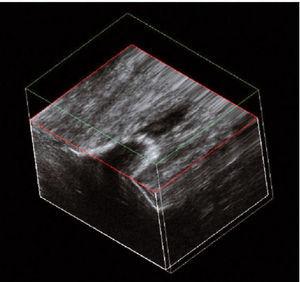

Este paciente presentaba dolor rotuliano crónico en relación con el ejercicio físico desde hacía varios años. El estudio longitudinal realizado con ambos equipos (E-A y E-B) permite observar una gran calcificación que invade la porción proximal del tendón31-34. Dicha calcificación produce una sombra acústica posterior (fig. 5A) visualizable de modo similar con ambos equipos (fig. 5B), aunque con el equipo E-B se observa la presencia de una zona hipoecoica amplia, próxima a la calcificación. Además, el E-B permite el estudio en 3D (fig. 6).

Figura 5 A) y B) La calcificación es fácilmente visualizable con ambos equipos, y se comprueba la sombra acústica posterior.

Figura 6 La imagen en 3 dimensiones del equipo E-B se obtiene mediante un barrido transversal con acumulación de imágenes sucesivas que permiten observar la calcificación en todos los planos.

El caso de la tendinosis calcificante del tendón rotuliano (caso 4), las imágenes obtenidas con ambos equipos (E-A y E-B) demuestran con nitidez la presencia de una gran calcificación que surge del polo inferior de la patela. Sin embargo, la utilización del sistema 3D en el equipo E-B supone una ventaja, pues permite visualizar en 3D la disposición de la calcificación29,30-32,36.